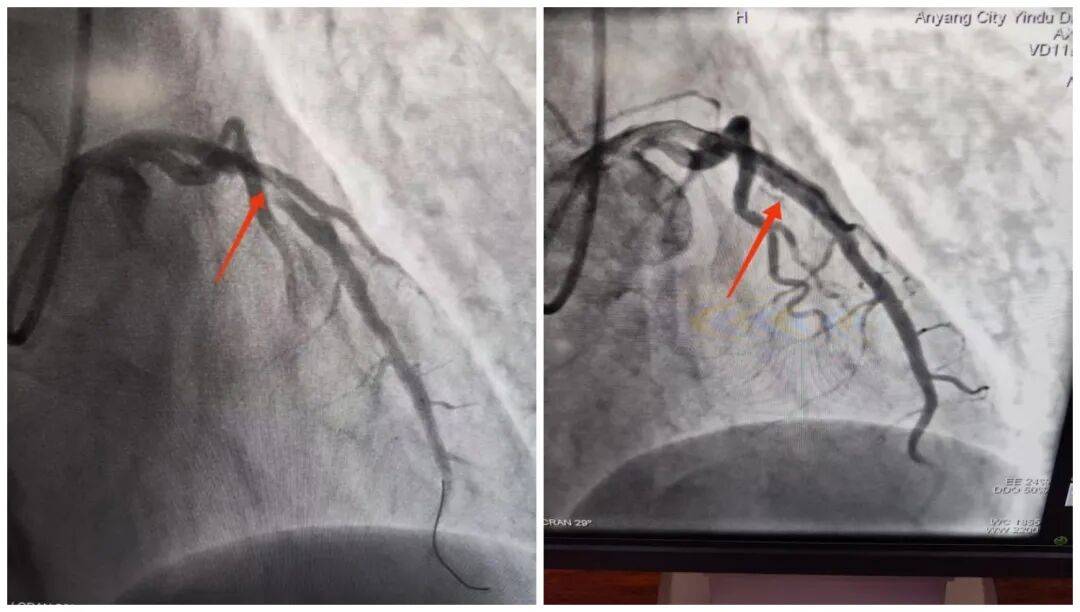

14:54,承載著生命希望的救護(hù)車抵達(dá)殷都區(qū)人民醫(yī)院大門口。14:56,劉大爺被推至導(dǎo)管室門口,早已等候在此的醫(yī)護(hù)團(tuán)隊(duì)立即上前,無縫銜接將劉大爺推進(jìn)導(dǎo)管室,手術(shù)隨即開始。15:18,醫(yī)院介入團(tuán)隊(duì)精準(zhǔn)操作,治療導(dǎo)絲成功通過病變部位,血管開通的關(guān)鍵一步順利完成。15:50,手術(shù)圓滿結(jié)束,成功挽救了瀕臨壞死的心肌。從劉大爺?shù)竭_(dá)殷都區(qū)人民醫(yī)院門口到成功開通堵塞血管,整個(gè)過程僅用了24分鐘,這一速度遠(yuǎn)優(yōu)于國(guó)際通行的90分鐘黃金標(biāo)準(zhǔn)。

此次對(duì)劉大爺?shù)某晒戎危⒎桥既唬恰靶碾娨粡埦W(wǎng)”打破診療壁壘、實(shí)現(xiàn)雙院高效聯(lián)動(dòng)的生動(dòng)實(shí)踐。曲溝衛(wèi)生院作為基層網(wǎng)絡(luò)醫(yī)院,在救治初期快速完成基礎(chǔ)檢查與初步處置,為后續(xù)治療“打底”;殷都區(qū)人民醫(yī)院專業(yè)團(tuán)隊(duì)則憑借精湛技術(shù)和高效協(xié)作,精準(zhǔn)“接力”,確保救治方案快速落地、手術(shù)順利推進(jìn)。兩者緊密配合,真正打通了轄區(qū)內(nèi)急性胸痛患者的分級(jí)救治綠色通道,為群眾的生命健康筑起了一道堅(jiān)實(shí)的“防護(hù)墻”。